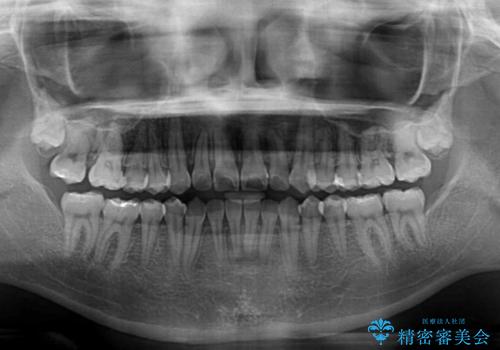

- 前歯のデコボコと奥歯の咬み合わせを気にして来院された患者様です。

右側の奥歯は、上が外側に転位した鋏状咬合を呈しており、前歯のデコボコ改善と並行して咬み合わせを改善していく必要がありました。

ワイヤー装置でもマウスピースでも、どちらでも適用の症例でしたが、片側の鋏状咬合はマウスピース矯正ではしっかりと改善できる可能性が低いことや、何と言っても自己管理の煩わしさがないことから、ワイヤー装置を選択されました。